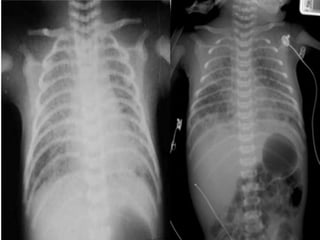

2-CXR :

* Bilateral alveolar densities with air

bronchograms are characteristic .

*Irregular patchy infiltrates or occasionally a

normal pattern also occur.

1- CultureS 2-CXR : *Bilateral alveolar densities with air bronchograms are characteristic . *Irregular patchy infiltrates or occasionally a normal pattern also occur.